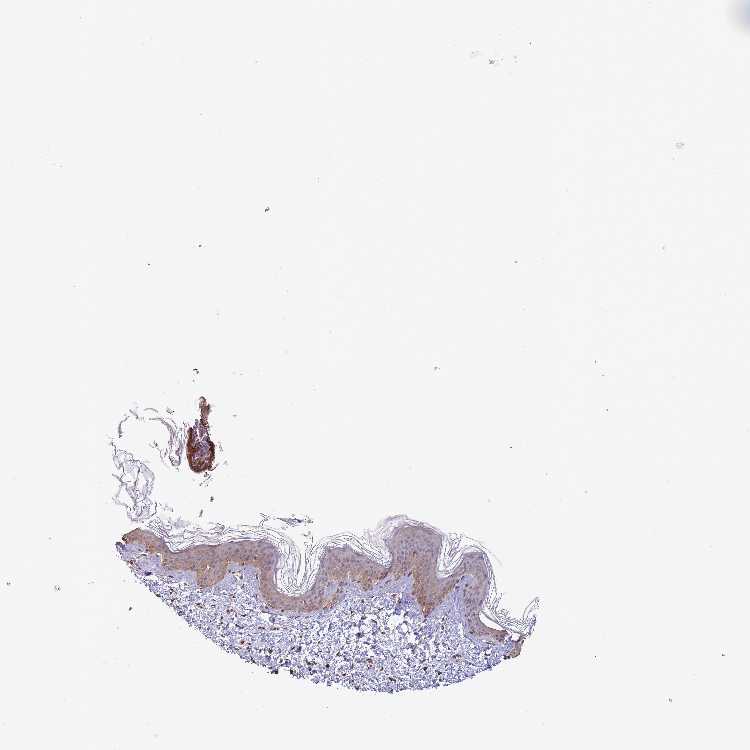

SKIN 1 - Antibody stainingi

Antibody staining in the annotated cell types in the current human tissue is reported as not detected, low, medium, or high, based on conventional immunohistochemistry profiling in selected tissues. This score is based on the combination of the staining intensity and fraction of stained cells.

Each image is clickable and will lead to virtual microscopy that enables deeper exploration of all samples and also displays staining intensity scores, fraction scores and subcellular localization as well as patient and tissue information for each sample.

Antibody HPA048926

Langerhans Medium

Fibroblasts High

Keratinocytes Medium

Melanocytes Medium

SKIN 2 - Antibody stainingi